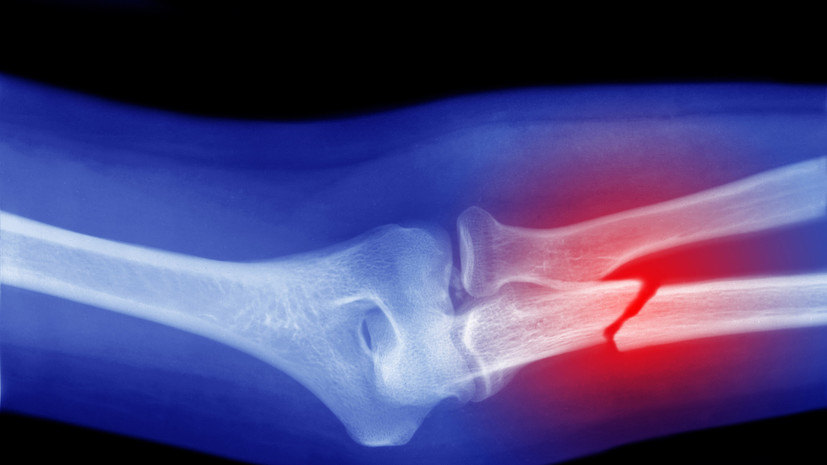

В беседе с «Газетой.Ru» специалист отметил, что при переломе костей нижних конечностей синяки и кровоподтёки могут распространиться по всей ноге, а также на пальцы или стопу.

«Уже через несколько минут может стать заметной деформация — видимое искривление кости или неестественное положение конечности», — сказал Бештоев.

По словам специалиста, при ушибе отёк и синяк будут развиваться медленно. Кожа может начать менять цвет только к вечеру или даже на следующий день, добавил врач.